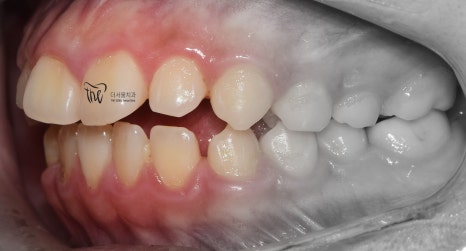

그리고, 정면 및 측면에서 본 모습으로는

살짝 개방교합(Open bite)의 형태를 보여줍니다.

그러면서, 치아들 간의 공간이 조금씩

떨어져 있는 것을 볼 수 있습니다.

마치, 치간이개와 같은 느낌을 받을 수 있으며

앞니들이 앞쪽으로 많이 뻐드러져 있는 형태를

띄고 있습니다.

이럴 경우에는, 무턱 의 증세가 더 뚜렷하게

나타날 수 밖에 없는 상황이 됩니다.